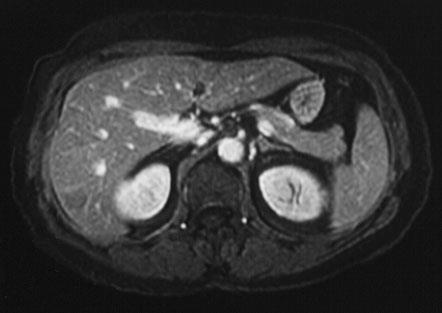

• Uses radio waves in the presence of a strong magnetic field that surrounds the opening of the MRI machine where the patient lies to get tissues to emit radio waves of their own.

• Different tissues emit a signal based on their chemical makeup, so a picture of the body organs is created.

• Risks:

• Generally Safe — so long as there is no metal in your body, there is no harmful radiation.

• Allergic reactions to the contrast agent

• The use of whole-body MRI is not recommended in asymptomatic patients who don’t have a genetic predisposition for cancer.

• Cost $400 - $12,000

• Varying rates of false positive results, additional testing can be resource exhaustive.

• Without the use of contrast in the MRI, it can overlook several cancers including colon, thyroid, and breast.